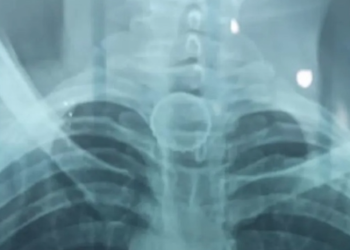

No AM, homem passa por cirurgia após abrir garrafa de cerveja e engolir a tampa

IPIXUNA (AM) – Durante a madrugada do Ano Novo (1º), um homem engoliu a tampa da cerveja após abrir a ...